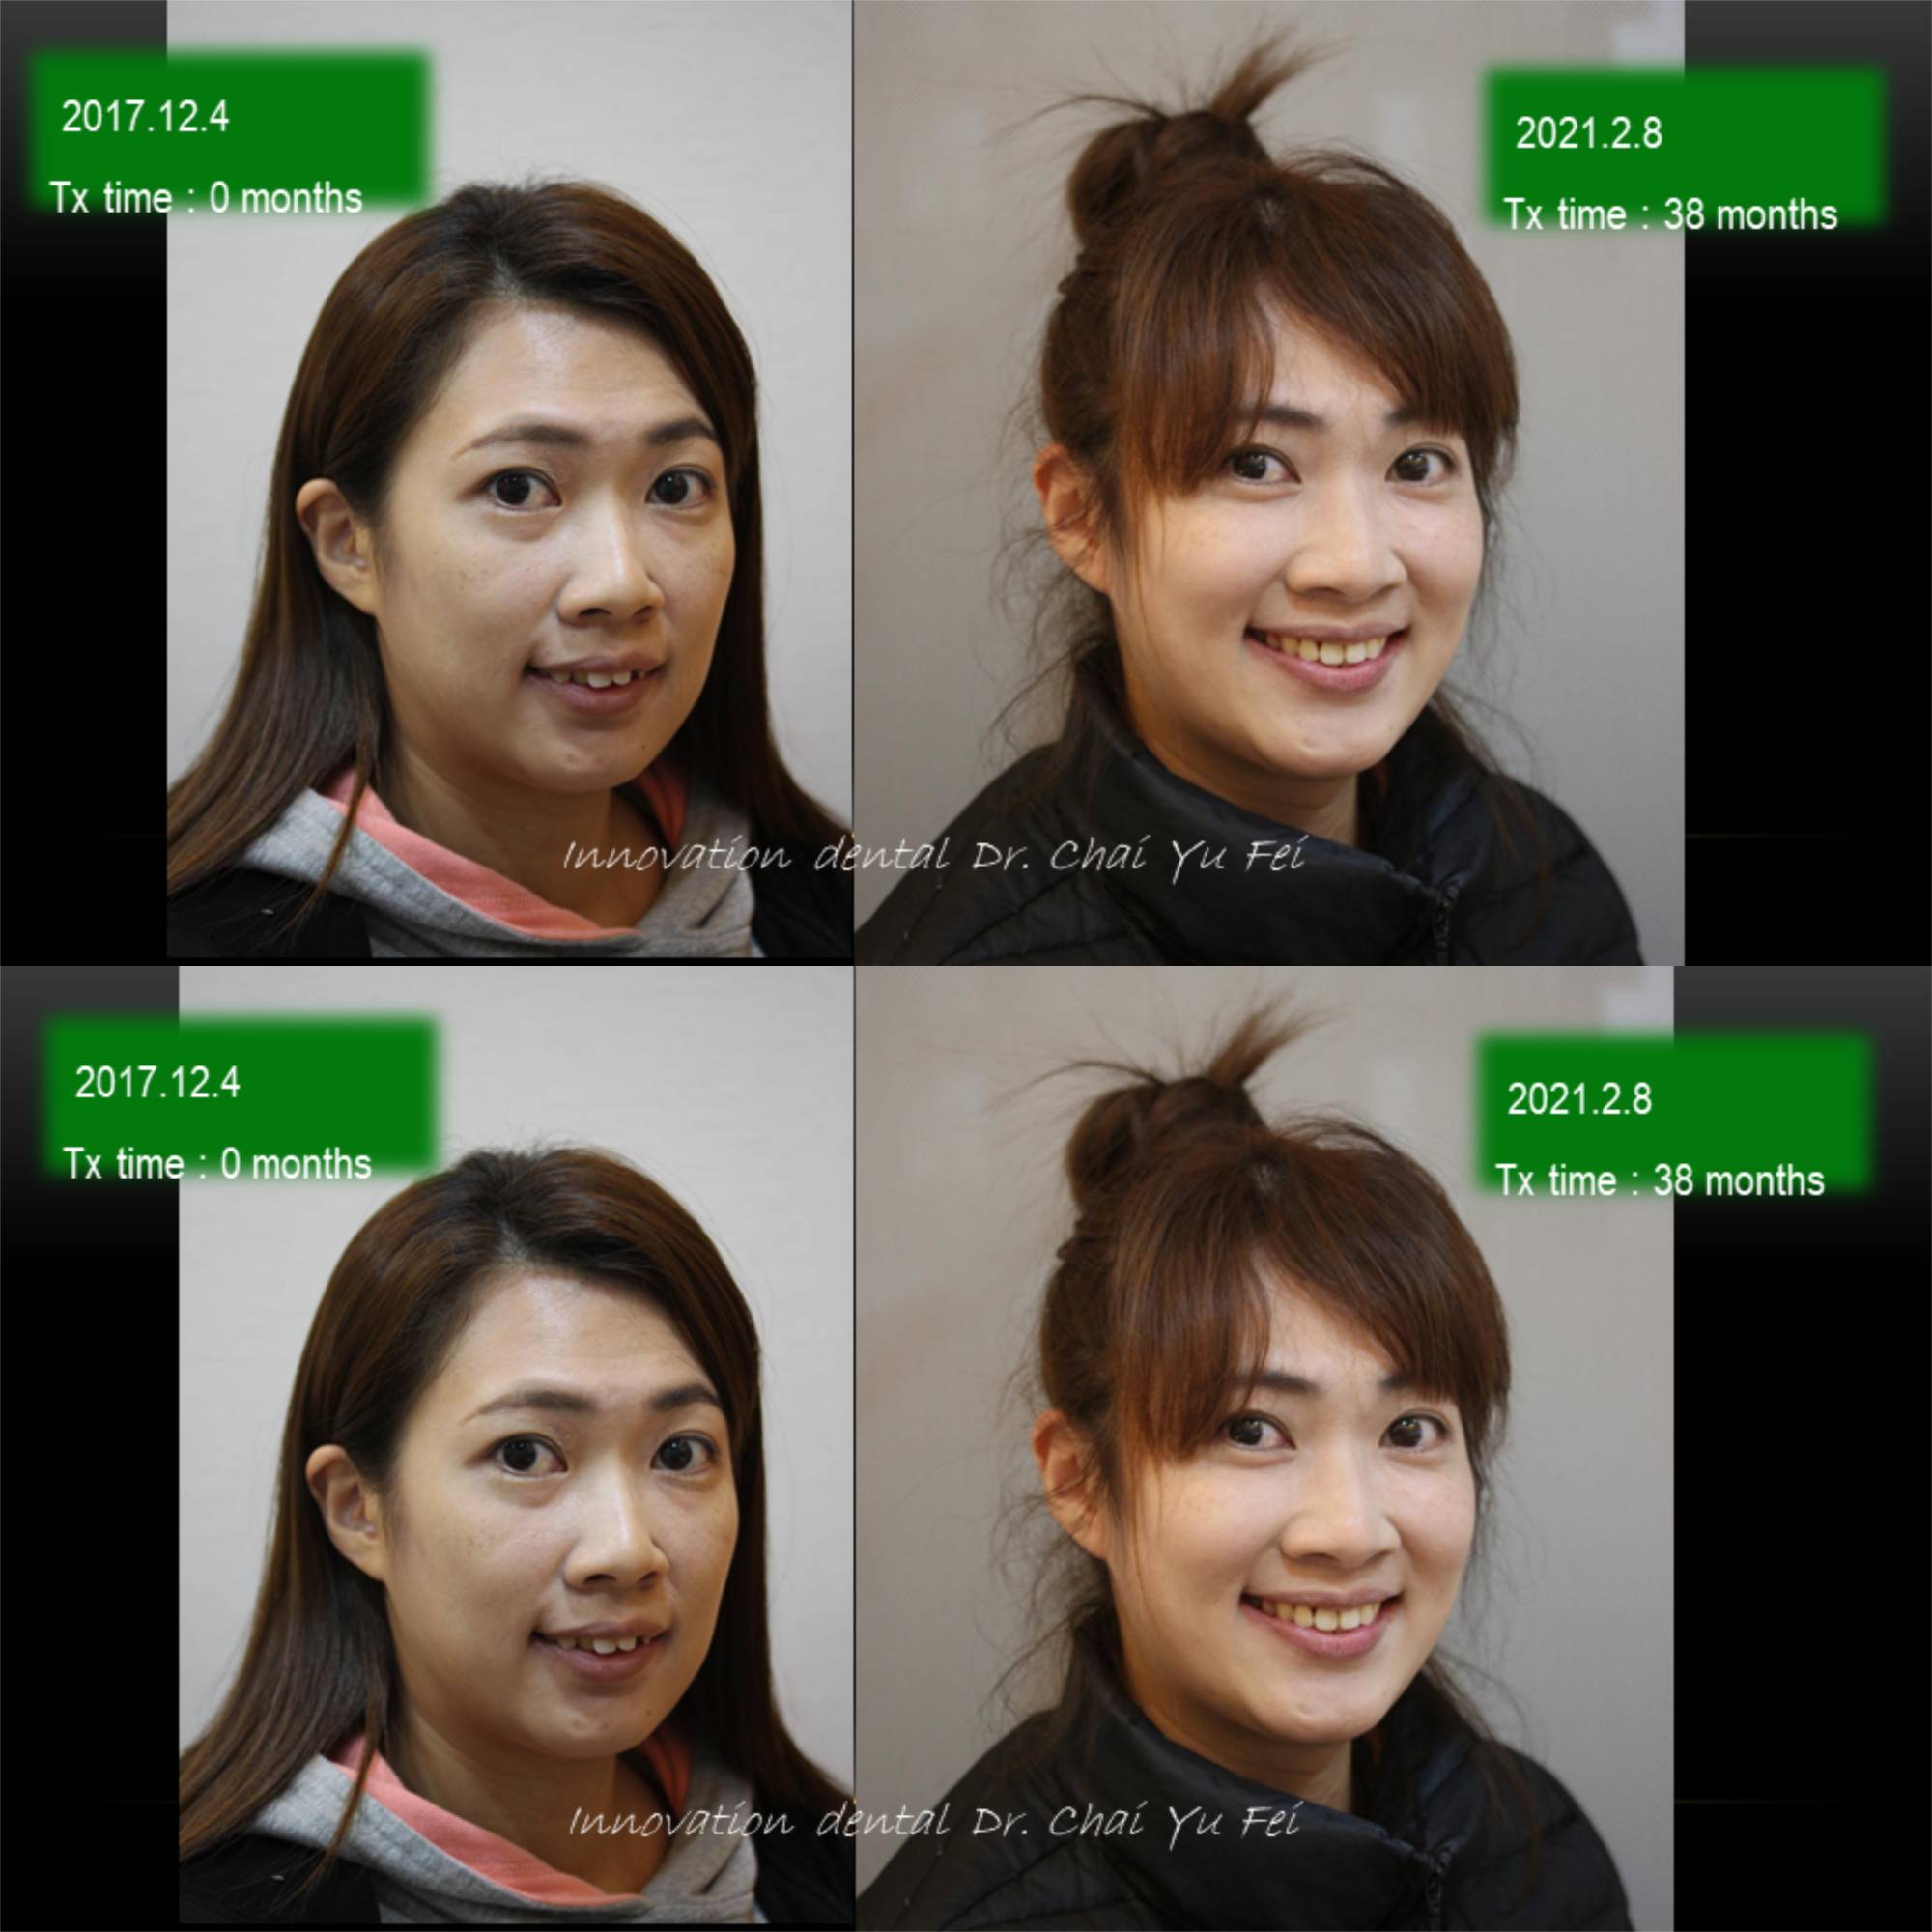

以這次黃小姐的案例來說,可以從照片中看到,由於上顎齒列狹窄,前牙角度往外傾斜,進而造成唇形前突不理想。

為了避免過度治療而傷害了原本可以恢復青春美麗的外觀,翟醫師決定採取上顎拔2顆小臼齒,下顎不要拔牙,在保留最多自然牙的情況下,改善下顎角度達到最美麗的外觀輪廓跟理想的咬合。

拔牙矯正前後變化,改善嘴型前突

看到這樣的治療結果,相信您應該對拔牙沒有那麼擔心了,不論是拔4顆或是拔2顆牙齒,我們無非都是為了讓出更多空間,來把齒列調整整齊,選擇拔牙的牙位通常也是重複性高的小臼齒,或是有病灶的牙齒,具有重要功能及不可取代性的牙齒我們不會隨便拔除,即使要犧牲牙齒,我們設計的治療計畫也會將犧牲降到最小,而且完全不影響功能以及外觀。治療完成後,一樣有好的微笑曲線跟理想穩定的咬合。